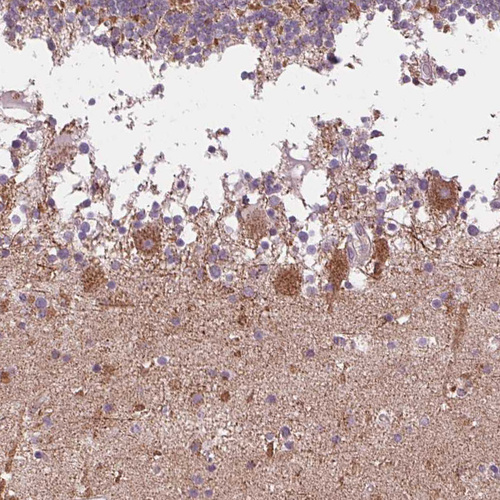

Immunohistochemical staining of human cerebellum shows moderate granular cytoplasmic positivity in Purkinje cells.